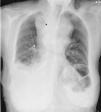

Chylothorax linked to goiter solved by transcervical total thyroidectomy without sternotomy

Quilotorax provocado por un bocio resuelto mediante tiroidectomía total con abordaje cervical sin esternotomía